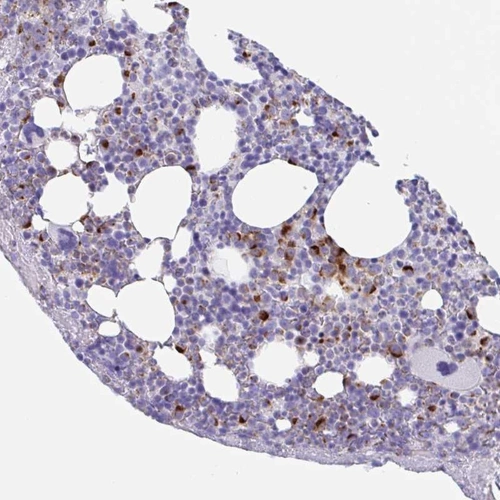

Immunohistochemical staining of human bone marrow shows strong cytoplasmic positivity in subset of hematopoietic cells.